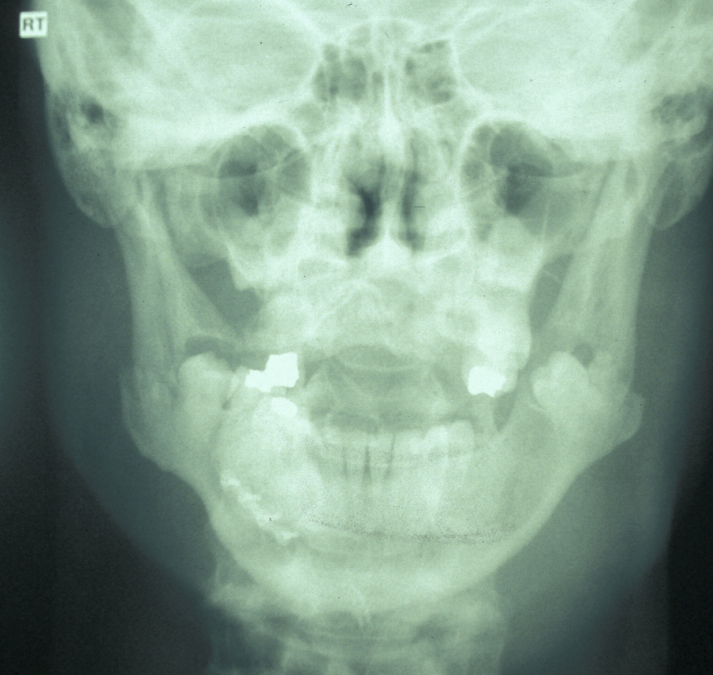

The combination of plain X-ray radiographs taken from different directions gives adequate diagnostic information for most mandibular fractures (DPT, dental panoramic tomogram (see Figure 2) and posteroanterior radiographs (see Figure 3)).

Figure 2: Dental panoramic tomogram showing bilateral mandibular angle fractures. Note the previous repair of a parasymphyseal fracture with a single body plate.

Figure 3: Posteroanterior radiograph of bilateral mandibular angle fractures. Same case as in Figure 2.